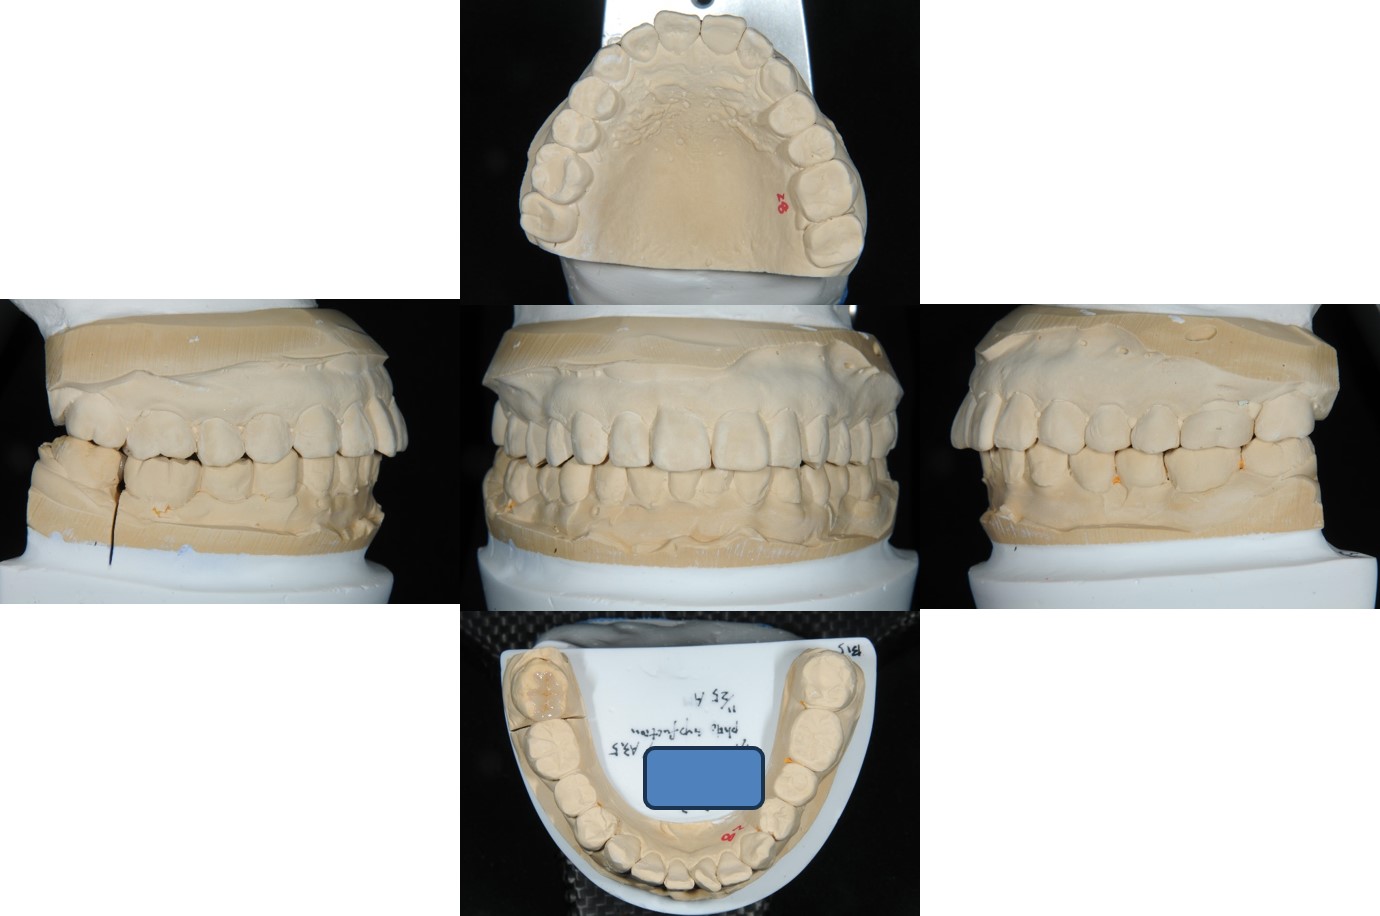

咬合器上製作瓷塊